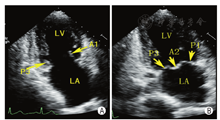

通过采集以下切面显示二尖瓣瓣叶各扇区。①胸骨旁左室长轴切面:显示A2、P2(图5A);②二尖瓣水平短轴切面:显示整个前后叶(图5B);③心尖四腔心切面:显示A2、P2(图6A);④心尖长轴切面:显示A2、P2(图6B);⑤心尖二腔心切面:显示A1、P3(图7A);⑥心尖二尖瓣交界处长轴切面:显示P1、A2、P3(图7B)。

TTE通过上述切面评价MR的机制、程度以及部位,并确定瓣膜运动异常的扇区。